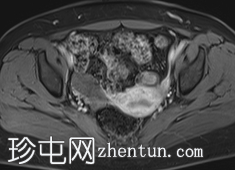

冠状位

T2加权像

双侧卵巢增大,间质体积明显增多,T2加权像呈弥漫性低信号,可见多个小卵泡。

右侧卵巢体积为27 cm³。

左侧卵巢体积为26 cm³,内含一个直径15 mm的囊肿,边缘呈锯齿状,周边强化。

未见可疑实性成分或异常增强。

MRI通常显示双侧对称性卵巢增大、均匀T2低信号和轻度间质强化。可见外周卵泡,但数量少于多囊卵巢综合征(PCOS)患者。这些发现与卵巢间质肥大和黄素化卵泡膜细胞相符,这些特征符合卵巢卵泡膜增生症的诊断。